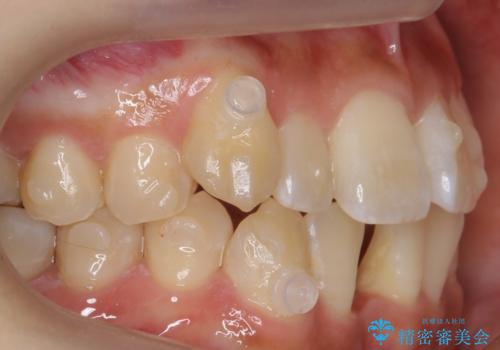

- 矯正装置

- インビザライン

- 治療期間

- 1年7ヶ月

- 治療回数

- 30回以上